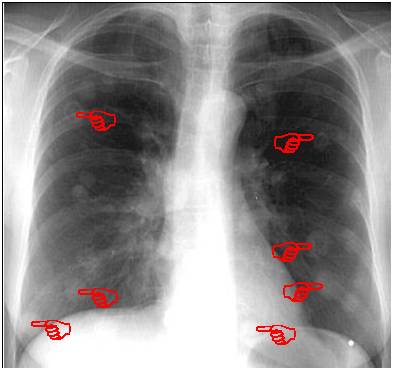

当然小编的手指指的并不是全部病灶,剩下的棉花团自己找吧!

胸片显示:两肺多发的大小不等的结节影,形如棉花团。

病理结果:宫颈癌肺转移。

4、最重要的X线表现:X线一般特点为两肺多发结节影,肺尖部稀少,两肺中、下野外带分布较多,晚期部分病灶可融合。大的像棉花团,小的像粟粒状,就是小米粒样。边缘光滑,多无分叶或毛刺。密度较淡,质地均匀。